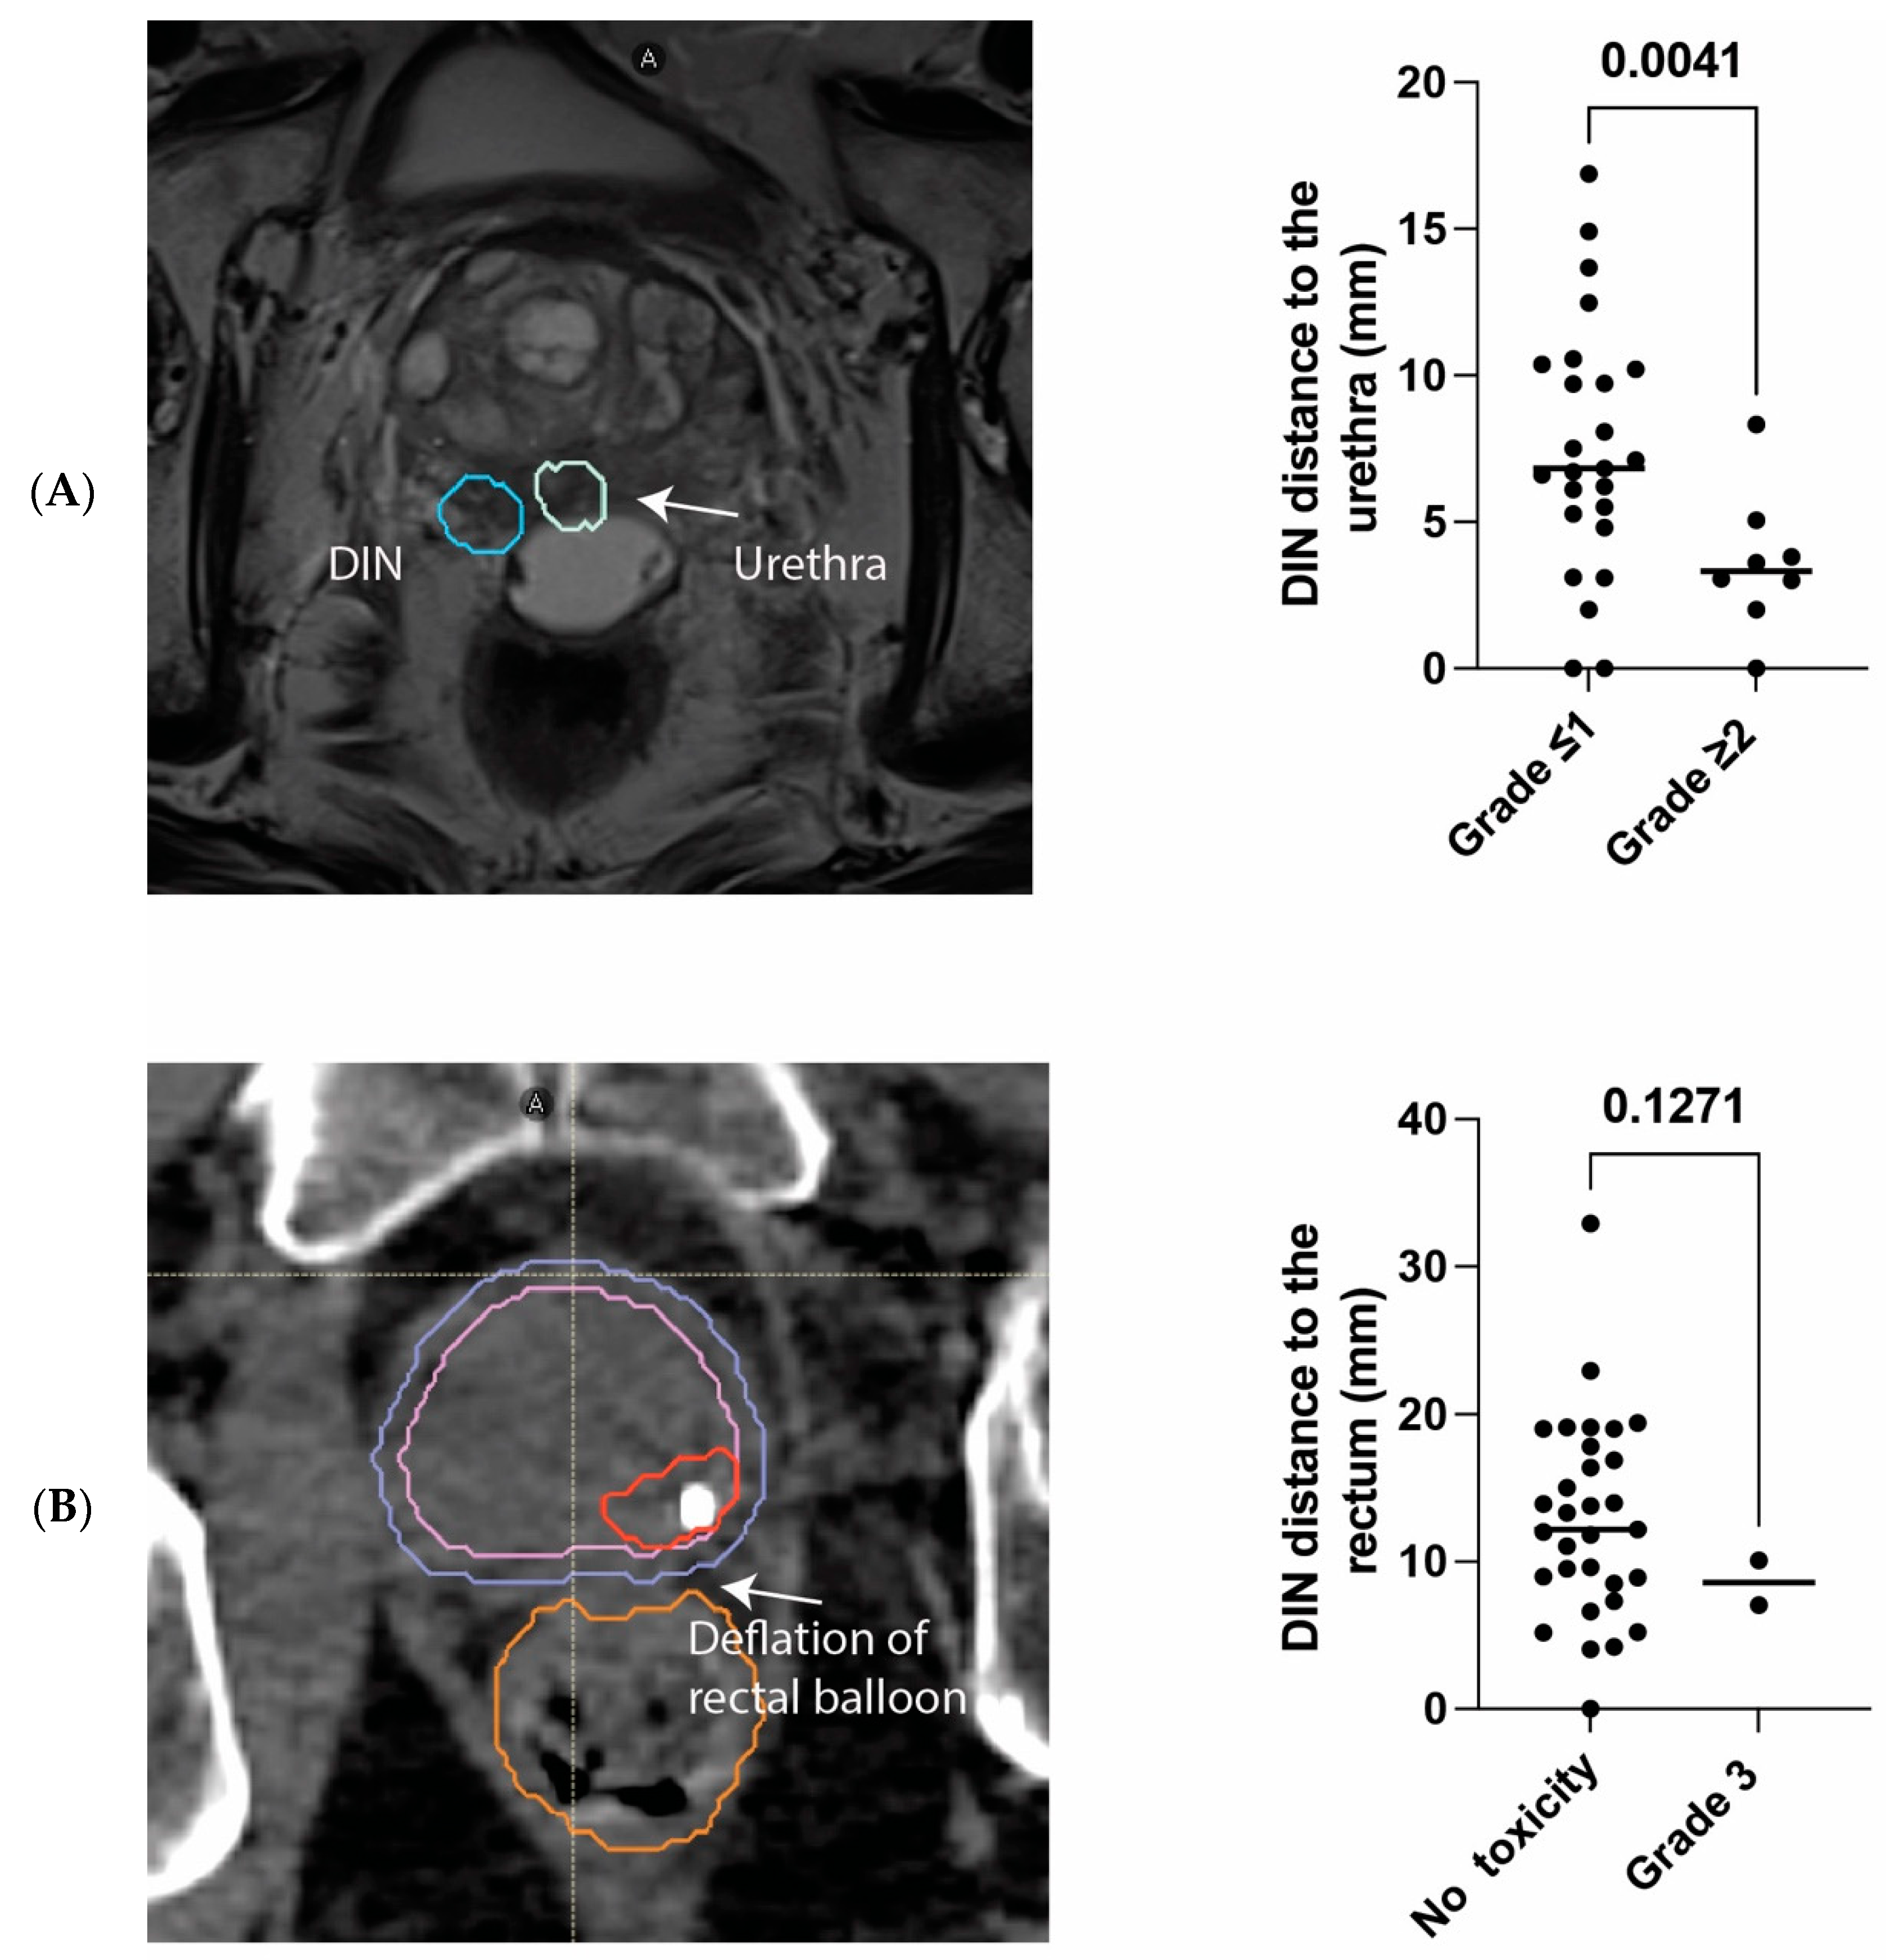

3.2. Safety